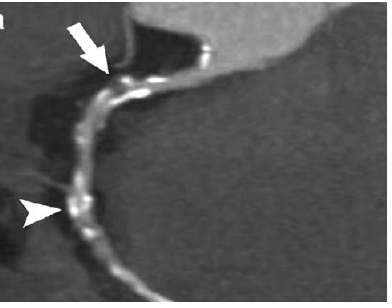

A Heart CT Scan - Right coronary artery MPR images show calcified plaque and non-calcified plaque (look at the arrow).